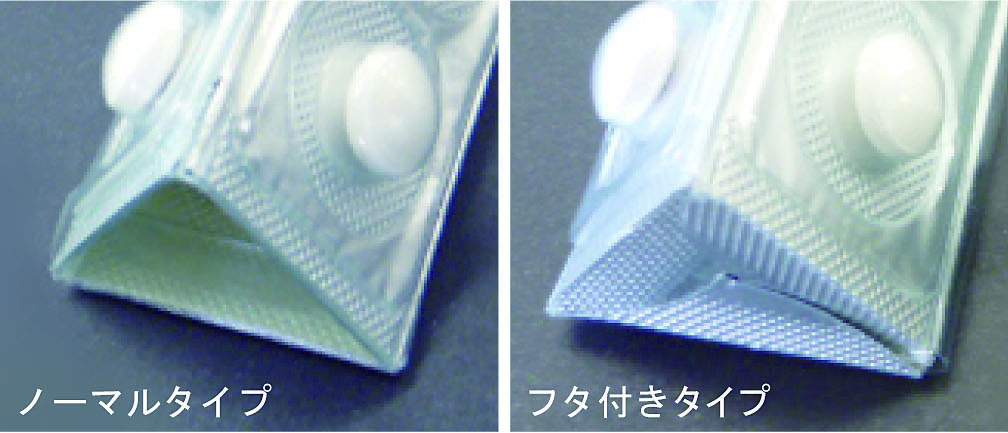

Http Www Morimoto Iyaku Jp Wp Content Img Sympo Downloadpage Esop Shoukai 151221 Pdf

Http Www Morimoto Iyaku Jp Wp Content Img Sympo Downloadpage Esop Shoukai 151221 Pdf